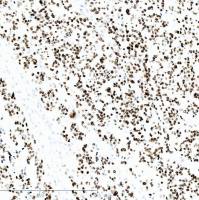

应用:CD4分子是存在于大多数辅助/诱导T细胞表面的59kDa的糖蛋白,为MHCⅡ类分子的受体,也是HIV的受体,其胞内部分与p56lck酪蛋白激酶相关,调节TCR/CD3复合体的功能。表达于辅助/诱导T淋巴细胞、髓细胞及组织细胞。可用于原发皮肤小/中等CD4+T细胞淋巴瘤的诊断,ALCL中CD4阳性多于CD8阳性,真正的组织细胞性淋巴瘤和母细胞性NK细胞淋巴瘤CD4阳性。主要用于T细胞淋巴瘤的分型。

阳性部位:细胞膜

阳性对照:扁桃体